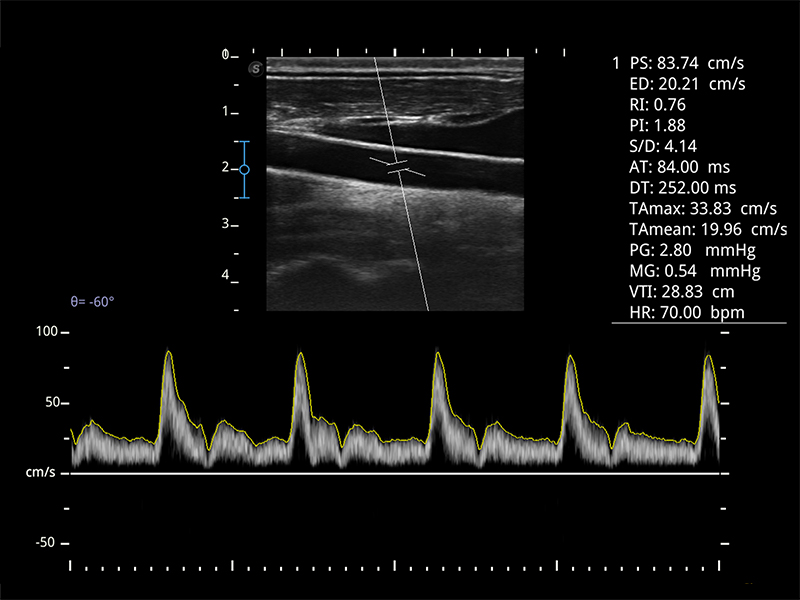

- Chroma per evidenziare i dettagli dell’immagine, migliorando la visibilità delle strutture vascolari.